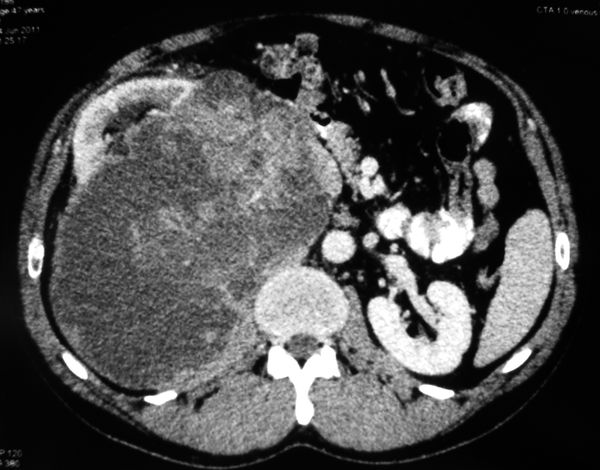

Бессимптомно растущие опухоли почек могут достигать гигантских размеров. Здесь и по ссылке такой случай. Схема на приложенном рисунке.